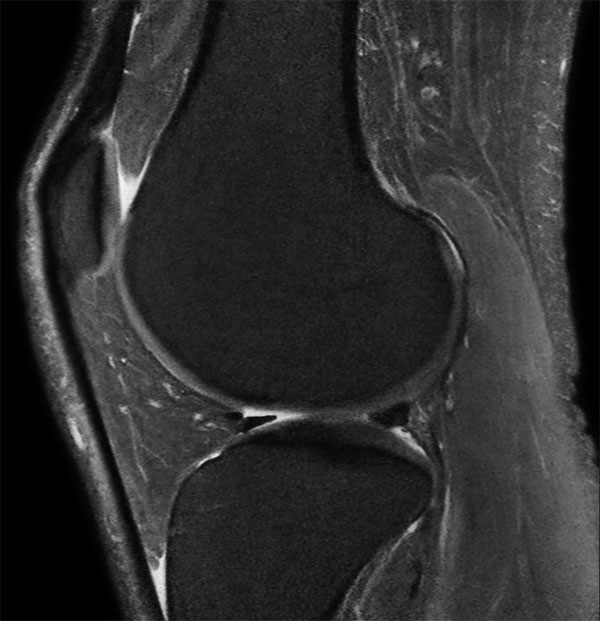

Middle aged board surfer presents with chronic knee pain. X-Ray shows no abnormalities. Follow-up MR examination requested.